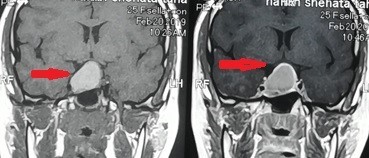

Magnetic resonance image of a patient suffering from a tumor of the skull base compressing the right optic nerve and the right carotid artery. Before and after successful microsurgical excision of the tumor.